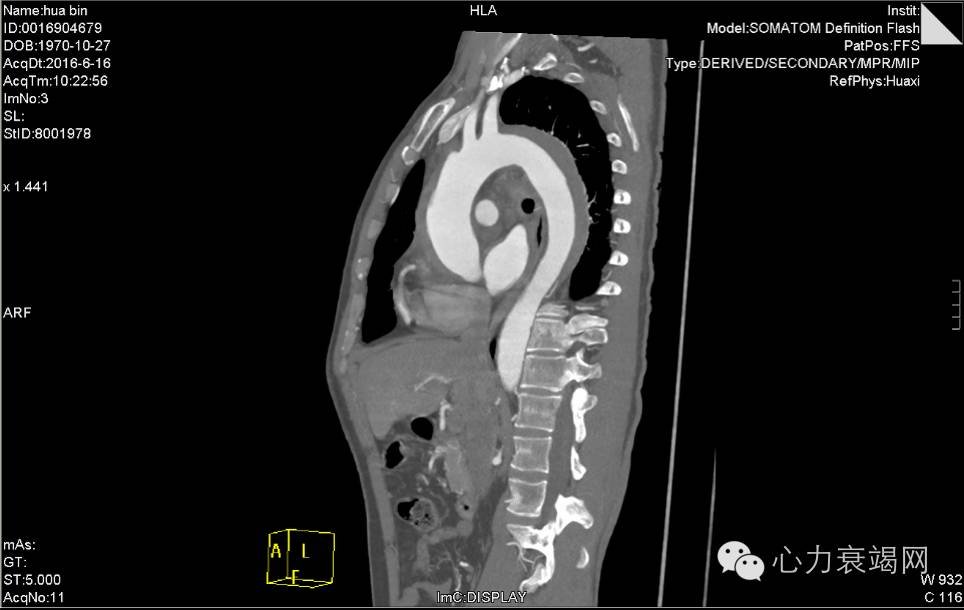

夹层动脉瘤CT

CTA示:主动脉壁内血肿,起自升主动脉根部,至降主动脉下段,并累及头臂干、左颈总动脉、左锁骨下动脉起始处,主动脉弓水平壁内血肿内见团片状低密度影,并见内膜小破口,增强见造影剂由破口进入壁内血肿,考虑局限性夹层?或其他,请结合临床。脾动脉稍迂曲。心脏稍增大,心包少许积液或心包增厚,主动脉壁少许钙化。双肺少许炎症,下叶为主。双侧胸腔少许积液或胸膜增厚。肝左外叶小囊肿。肝右后叶钙化灶。左肾囊肿。